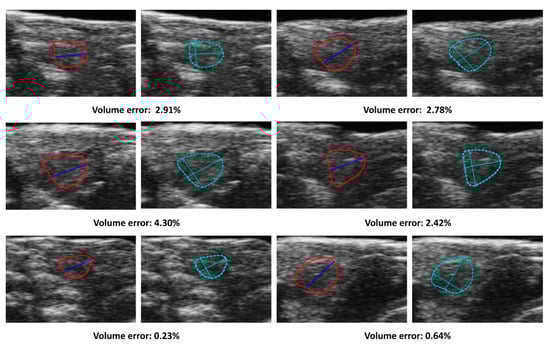

Figure 2.

Unsupervised segmentation trials utilizing different methods failed to detect expected masks. Each image is represented by a distinct color, signifying the model-generated segmentation regions. (a) An original frame, where individuals without training could not accurately classify the ventricle’s location due to the lack of ground truth labels; (b) An expected mask created manually; (c) A result frame obtained using modified CNNs revealing that the model is susceptible to color interference and, as such, is unsuitable for echo-videos; (d) A result of Dino demonstrating the model was incapable of detecting the ventricle due to background noise.

Dino, an implementation of self-supervised learning on Vision Transformers (ViTs) [20], was applied for unsupervised video segmentation(Figure 2d). Dino employs a simplified self-supervised training approach by predicting the output of a teacher network. It comprises a momentum encoder and uses a standard cross-entropy loss. Dino has two key features that distinguish it from CNNs and supervised ViTs: it explicitly encodes semantic information about image segmentation such as scene layout and object boundaries.

However, these methods are not robust enough to handle echo-video’s blurring and signal noise, making them unsuitable for the image segmentation task and ejection fraction assessment. As a result, supervised image segmentation has been the only method to demonstrate sufficient accuracy in this work.